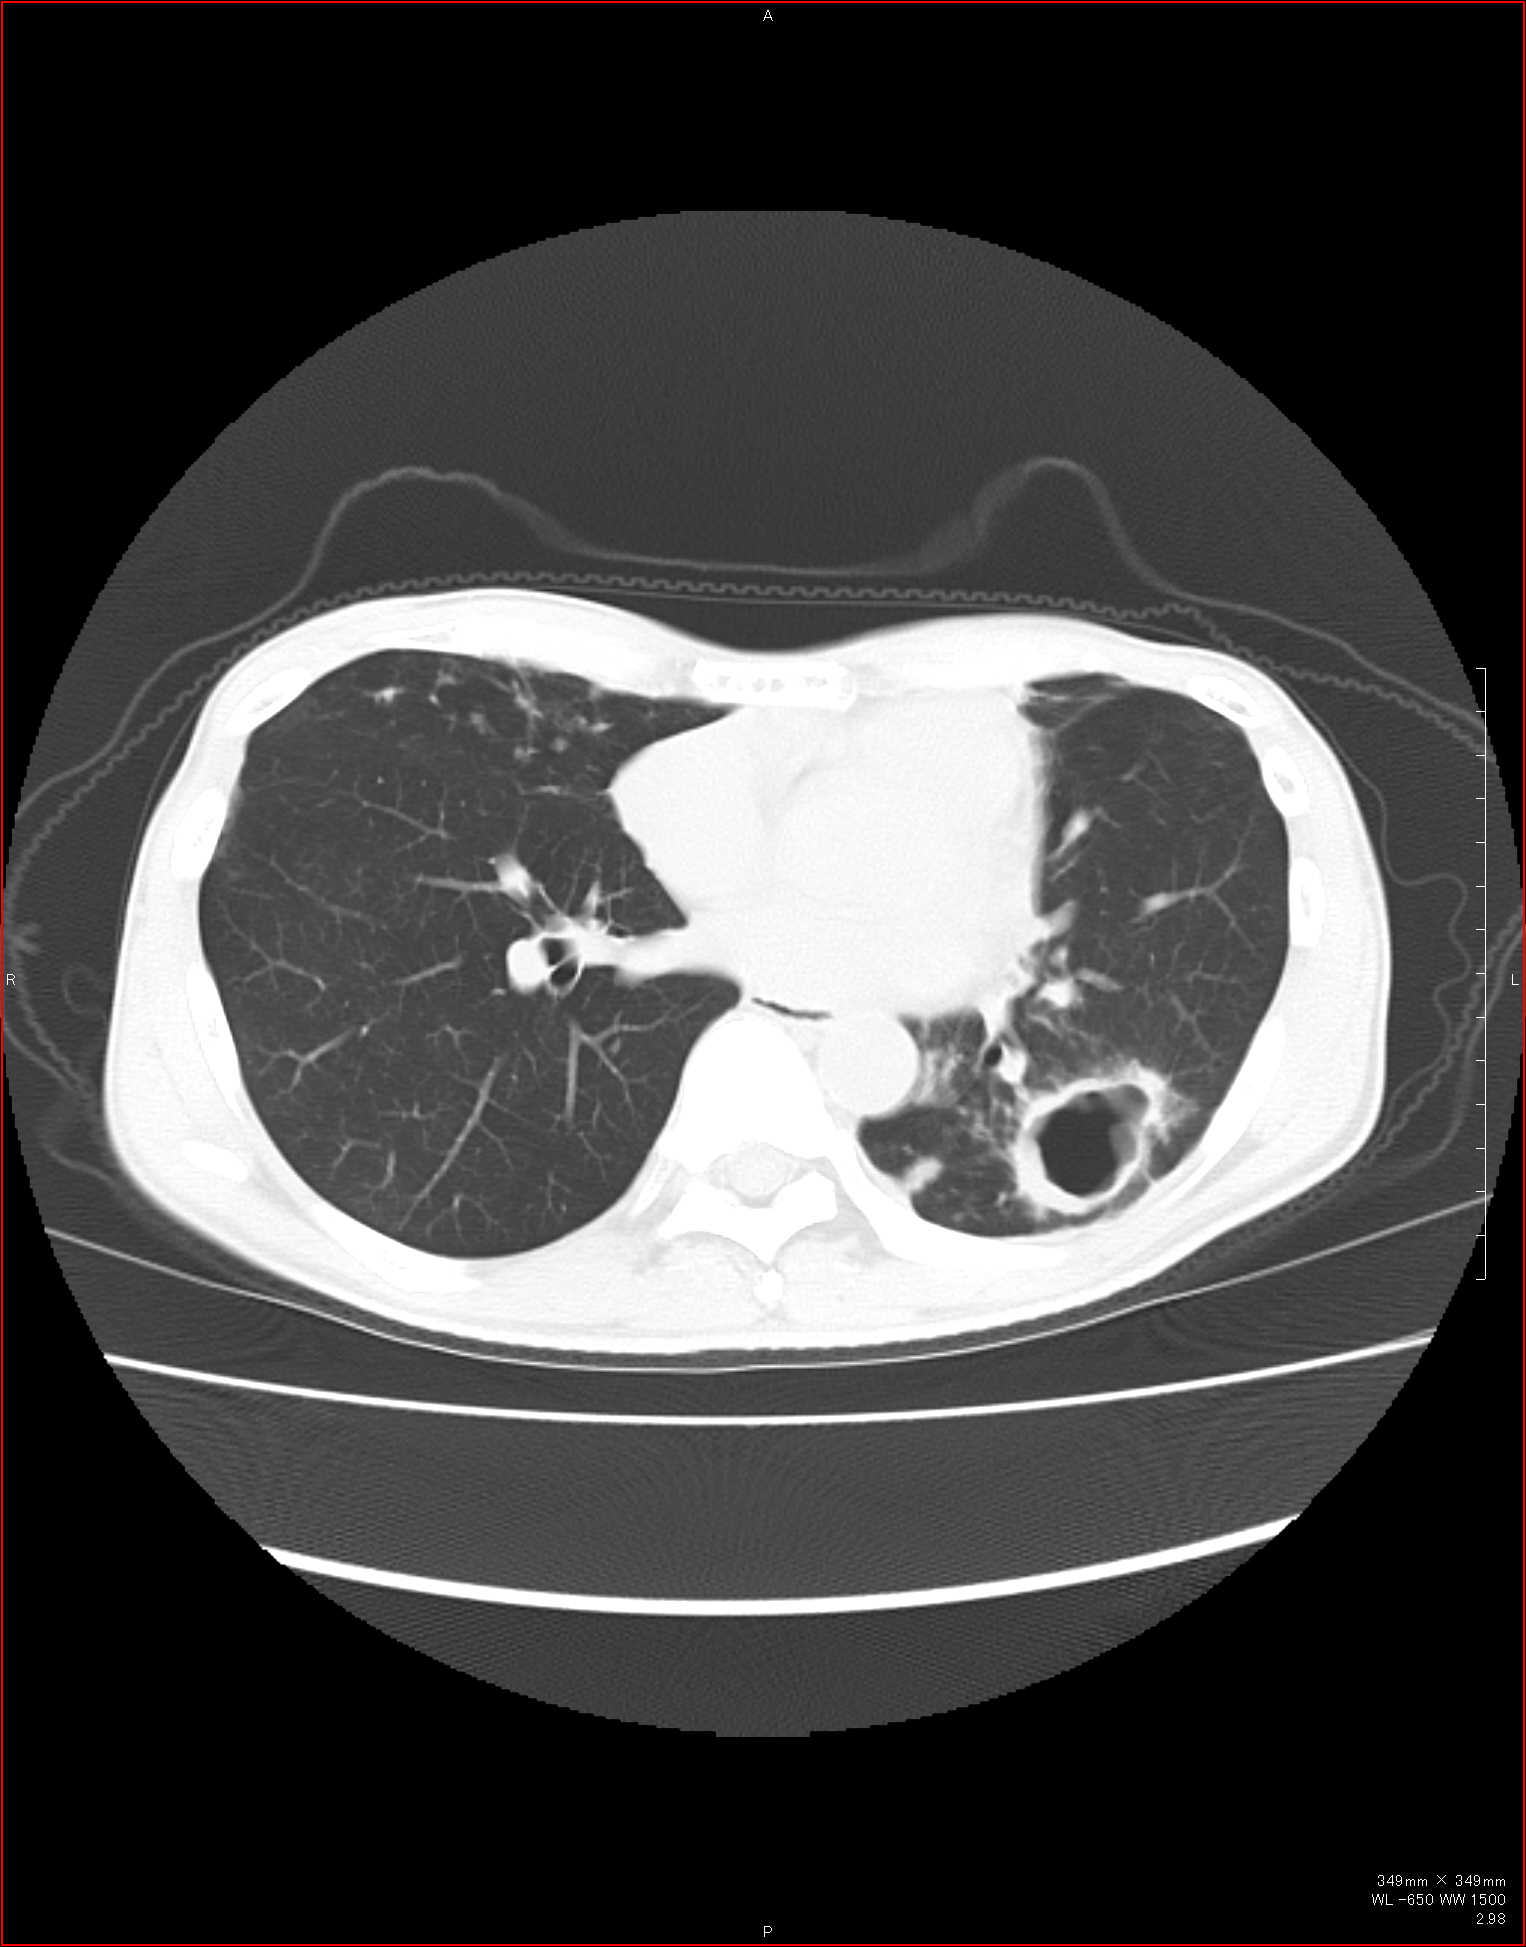

CTで見ると…

3Dだと、こうなります。

気管狭窄ですね。こういう所見もレントゲンで捉えることができるのです。